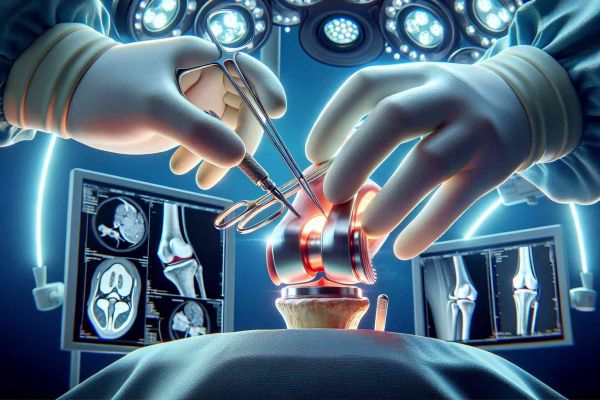

Αρθροπλαστική γόνατος ελάχιστης επεμβατικότητας (Minimally Invasive Surgery)

Η αρθροπλαστική ελάχιστης επεμβατικότητας χρησιμοποιεί εξειδικευμένα εργαλεία τα οποία προσαρμόζουν με ακρίβεια δια μέσου μικρών τομών. Η ελάχιστη διαταραχή στους ιστούς πέρα από το άριστο κοσμητικό αποτέλεσμα έχει αρκετά πλεονεκτήματα.

Ρομποτική αρθροπλαστική γόνατος

Ψηφιακά υποβοηθούμενη αρθροπλαστική γόνατος CAOS

Πρόκειται για την εφαρμογή της ψηφιακής τεχνολογίας στην αρθροπλαστική. Χρησιμοποιείται δηλαδή υπολογιστής μέσω των μετρήσεων του οποίου επιτυγχάνεται η ορθή τοποθέτηση των υλικών.

H κατάλληλη τοποθέτηση των προθέσεων (τεχνητών αρθρώσεων) φαίνεται να είναι ο ουσιώδης παράγοντας ο οποίος καθορίζει την καλή λειτουργία και επιβίωση μιας τεχνητής άρθρωσης.

Εξατομικευμένη αρθροπλαστική γόνατος CFTKR

Το “εξατομικευμένο γόνατο” αποτελεί τεχνική που ακολουθεί την τεχνολογική εξέλιξη στην νέα γενιά αρθοπλαστικών. Με την τεχνική αυτή ο ασθενής υποβάλλεται σε μαγνητική ή αξονική τομογραφία γόνατος 20 ημέρες πριν το χειρουργείο.

Στην συνέχεια με ειδικό λογισμικό αναλύεται και αποστέλλεται αυτή σε εξειδικευμένο κέντρο του εξωτερικού. Ακολουθεί η γραμμή παραγωγής στην οποία σχεδιάζονται ειδικά εργαλεία για τη διαμόρφωση της άρθρωσης ώστε να δεχθεί την πρόθεση του γόνατος.